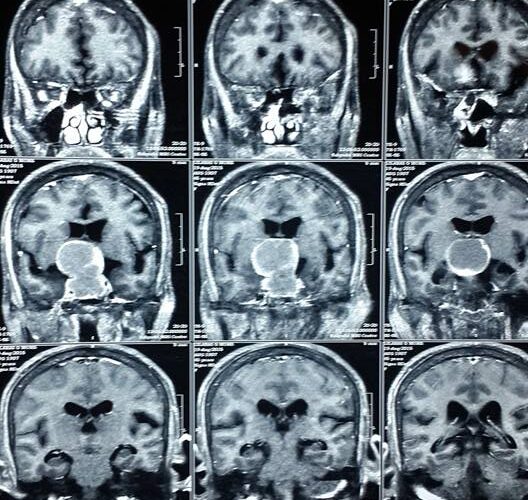

3 Endoscopic Pituitary Cases in Manik Hospital